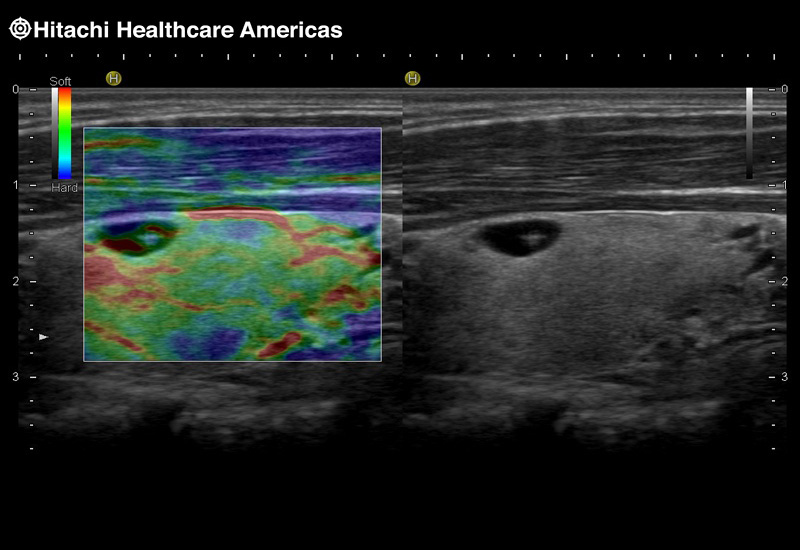

Imaging Clearly Defined

State-of-the-art digital architecture and advanced imaging features to redefine the capabilities of surgical ultrasound.

Arietta 70

Recognized for our outstanding image quality, outstanding system reliability and intuitive use of cutting edge technology, Fujifilm Healthcare remains the standard in the field of Surgery.

Fujifilm Healthcare’s ARIETTA Precision features state-of-the-art digital architecture and advanced imaging technologies to redefine the capabilities of surgical ultrasound.